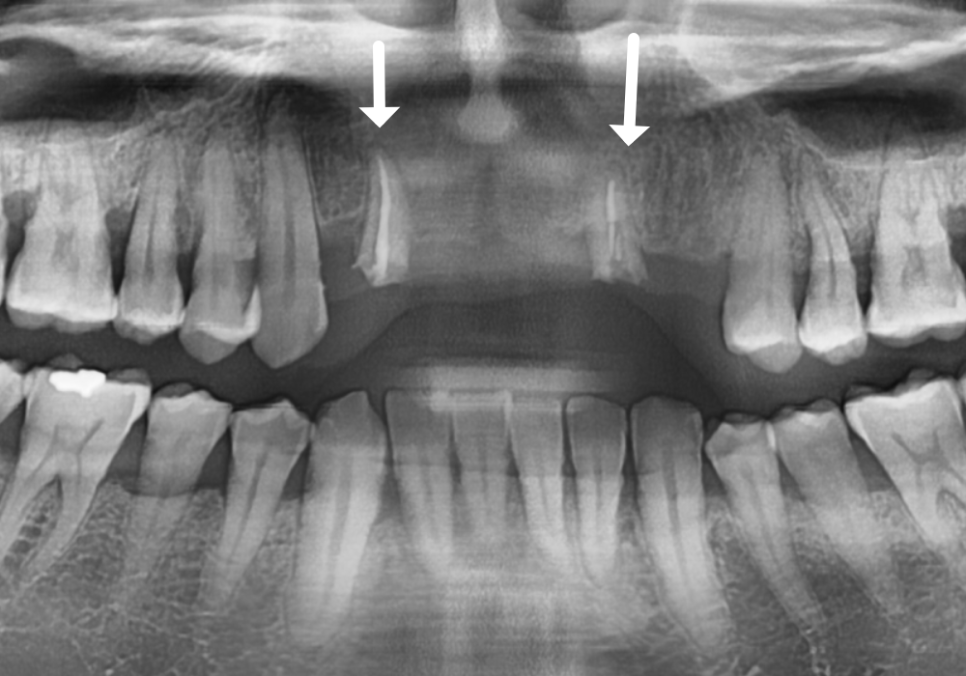

이번 환자분의 경우에도 CT를 분석해 보니

다행히 뼈의 폭이 5mm~7mm 정도로

충분히 두꺼웠습니다.

뼈의 폭이 충분하다면

굳이 뼈이식을 할 필요가 없습니다.^^

이 환자분은 뼈가 건강하셨기에

추가적인 뼈이식 없이

총 3대의 임플란트를

정확한 위치에 식립해 드렸습니다.